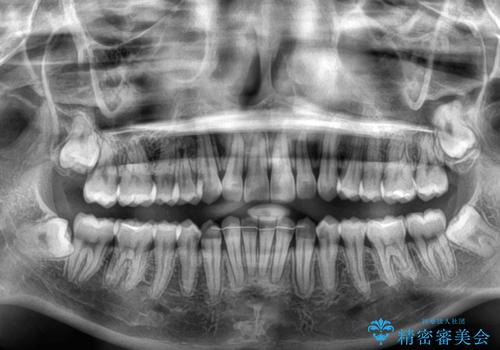

- 上下前歯の重なりを気にして来院された患者様です。

安価なインビザラインパッケージを用いての治療を希望されており、デコボコの程度が中等度であったため、インビザライン・モデレートを用いて矯正治療を行うこととしました。

インビザライン・モデレートは、製作できるアライナーの枚数に制限があるため、移動可能な量に限りがあるものの、インビザライン・ライトよりも枚数が多いため、幅広い症例に対応可能です。